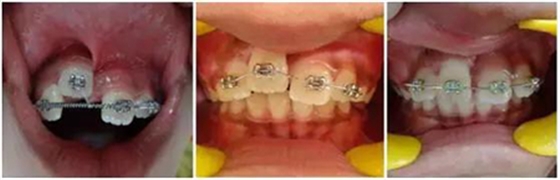

正畸牽引觀察其復(fù)位情況: 先觀察挫入的牙齒在未干預(yù)的情況下自發(fā)復(fù)位的情況。經(jīng)過3周的觀察,牙12復(fù)位,但牙11沒有顯示出復(fù)位的跡象。因此,使用MBT托槽正畸牽引牙11復(fù)位。為了讓其沿正確的方向復(fù)位,使用橡皮圈以獲得緩慢持續(xù)的牽引力(圖3)。

(圖3)

正畸牽引5周后,牙齒復(fù)位到其原始位置,與其他切牙完全對齊(圖3)。開始嘗試血運(yùn)重建。重新打開根管,使用次氯酸鈉和生理鹽水沖洗。然后插入無菌根管銼,并將其推到根尖處,以使血流進(jìn)入根管。一旦血液到達(dá)釉牙骨質(zhì)界,放置一個濕潤的無菌棉球靜置15分鐘,直到血凝塊形成,再放置約2-3mm的MAT在血凝塊上。在MAT上覆蓋一個濕棉球,隨后進(jìn)行臨時修復(fù)。以后再替換為玻璃離子水門汀墊底和復(fù)合樹脂修復(fù)。復(fù)診時間為1、3、6、9和12月。正畸復(fù)位保留12周。然而,在這么長的保留期內(nèi)還是復(fù)發(fā)了錯位,這也強(qiáng)調(diào)了在嚴(yán)重侵入的情況下長期復(fù)位的重要性,因?yàn)槔奂暗难例X周圍出現(xiàn)大量的牙槽骨喪失(圖 4)。